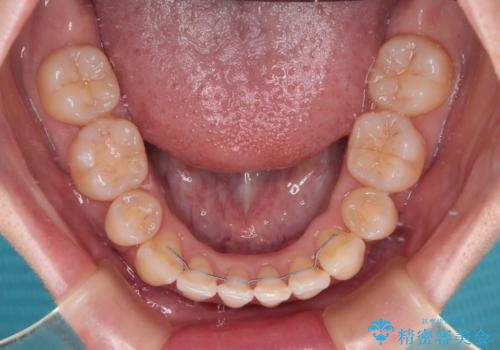

- メタルブラケット

- 2年2ヶ月

上下ともに歯列が前方に突出していたため、上下左右の第一小臼歯4本を抜去し、ワイヤー装置による矯正治療を行うこととしました。

舌の突出癖がなかなか改善されず、上下前歯の接触がやや甘い状態での仕上がりとなりました。

接触が甘い場合、上顎前歯の叢生が後戻りを起こしやすくなるため、治療終了後の保定期間でも舌のトレーニングを継続するように指示しています。